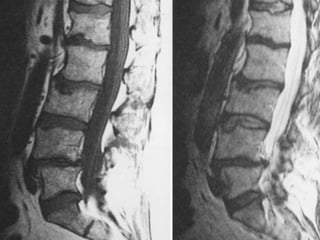

Occult Fracture

75 wm severe! LBP S/P cement 6 months ago